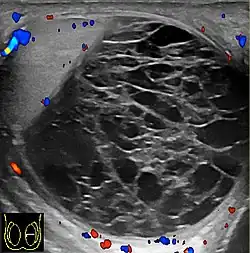

However, these patterns, except the latter one, may be considered as non-specific as heterogeneous echotexture and shadowing calcification can also be detected in malignant testicular tumors. The onion peel pattern of epidermoid cyst [Fig. 10] correlates well with the pathologic finding of multiple layers of keratin debris produced by the lining of the epidermoid cyst. This sonographic appearance should be considered characteristic of an epidermoid cyst and corresponds to the natural evolution of the cyst. Absence of vascular flow is another important feature that is helpful in differentiation of epidermoid cyst from other solid intratesticular lesions.